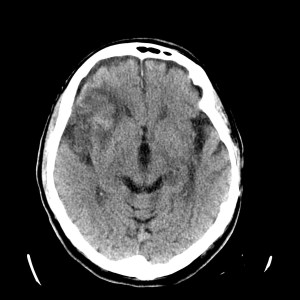

Se investiga un poco más y se descubre que el paciente había acudido diez días antes, también con cierta clínica de debilidad en hemicuerpo izquierdo, y se le realizó un TAC de cráneo. Observemos por tanto el estudio previo:

Pues bien, ante los hallazgos descritos, se clarifica que estamos ante un paciente el cual no tiene una masa y que ha sufrido una lesión isquémica hace diez días. Ahora, sobre dicha lesión, tenemos una imagen con un aumento de densidad que sugiere sangrado por una parte y otra hipodensidad en la perifería que correspondería a un edema. Por tanto, descartamos un sangrado intraparenquimatoso de novo. El paciente tiene más de 65 años, no es hipertenso, la imagen del sangrado no es de alta densidad, lo que se opone a una fase aguda o hiperaguda, y tenemos el TC de cráneo previo donde ya se advertía un proceso de tipo isquémico. Por tanto, nos quedan dos opciones, o estamos ante un resangrado de un ACV o estamos ante una Perfusión de lujo.